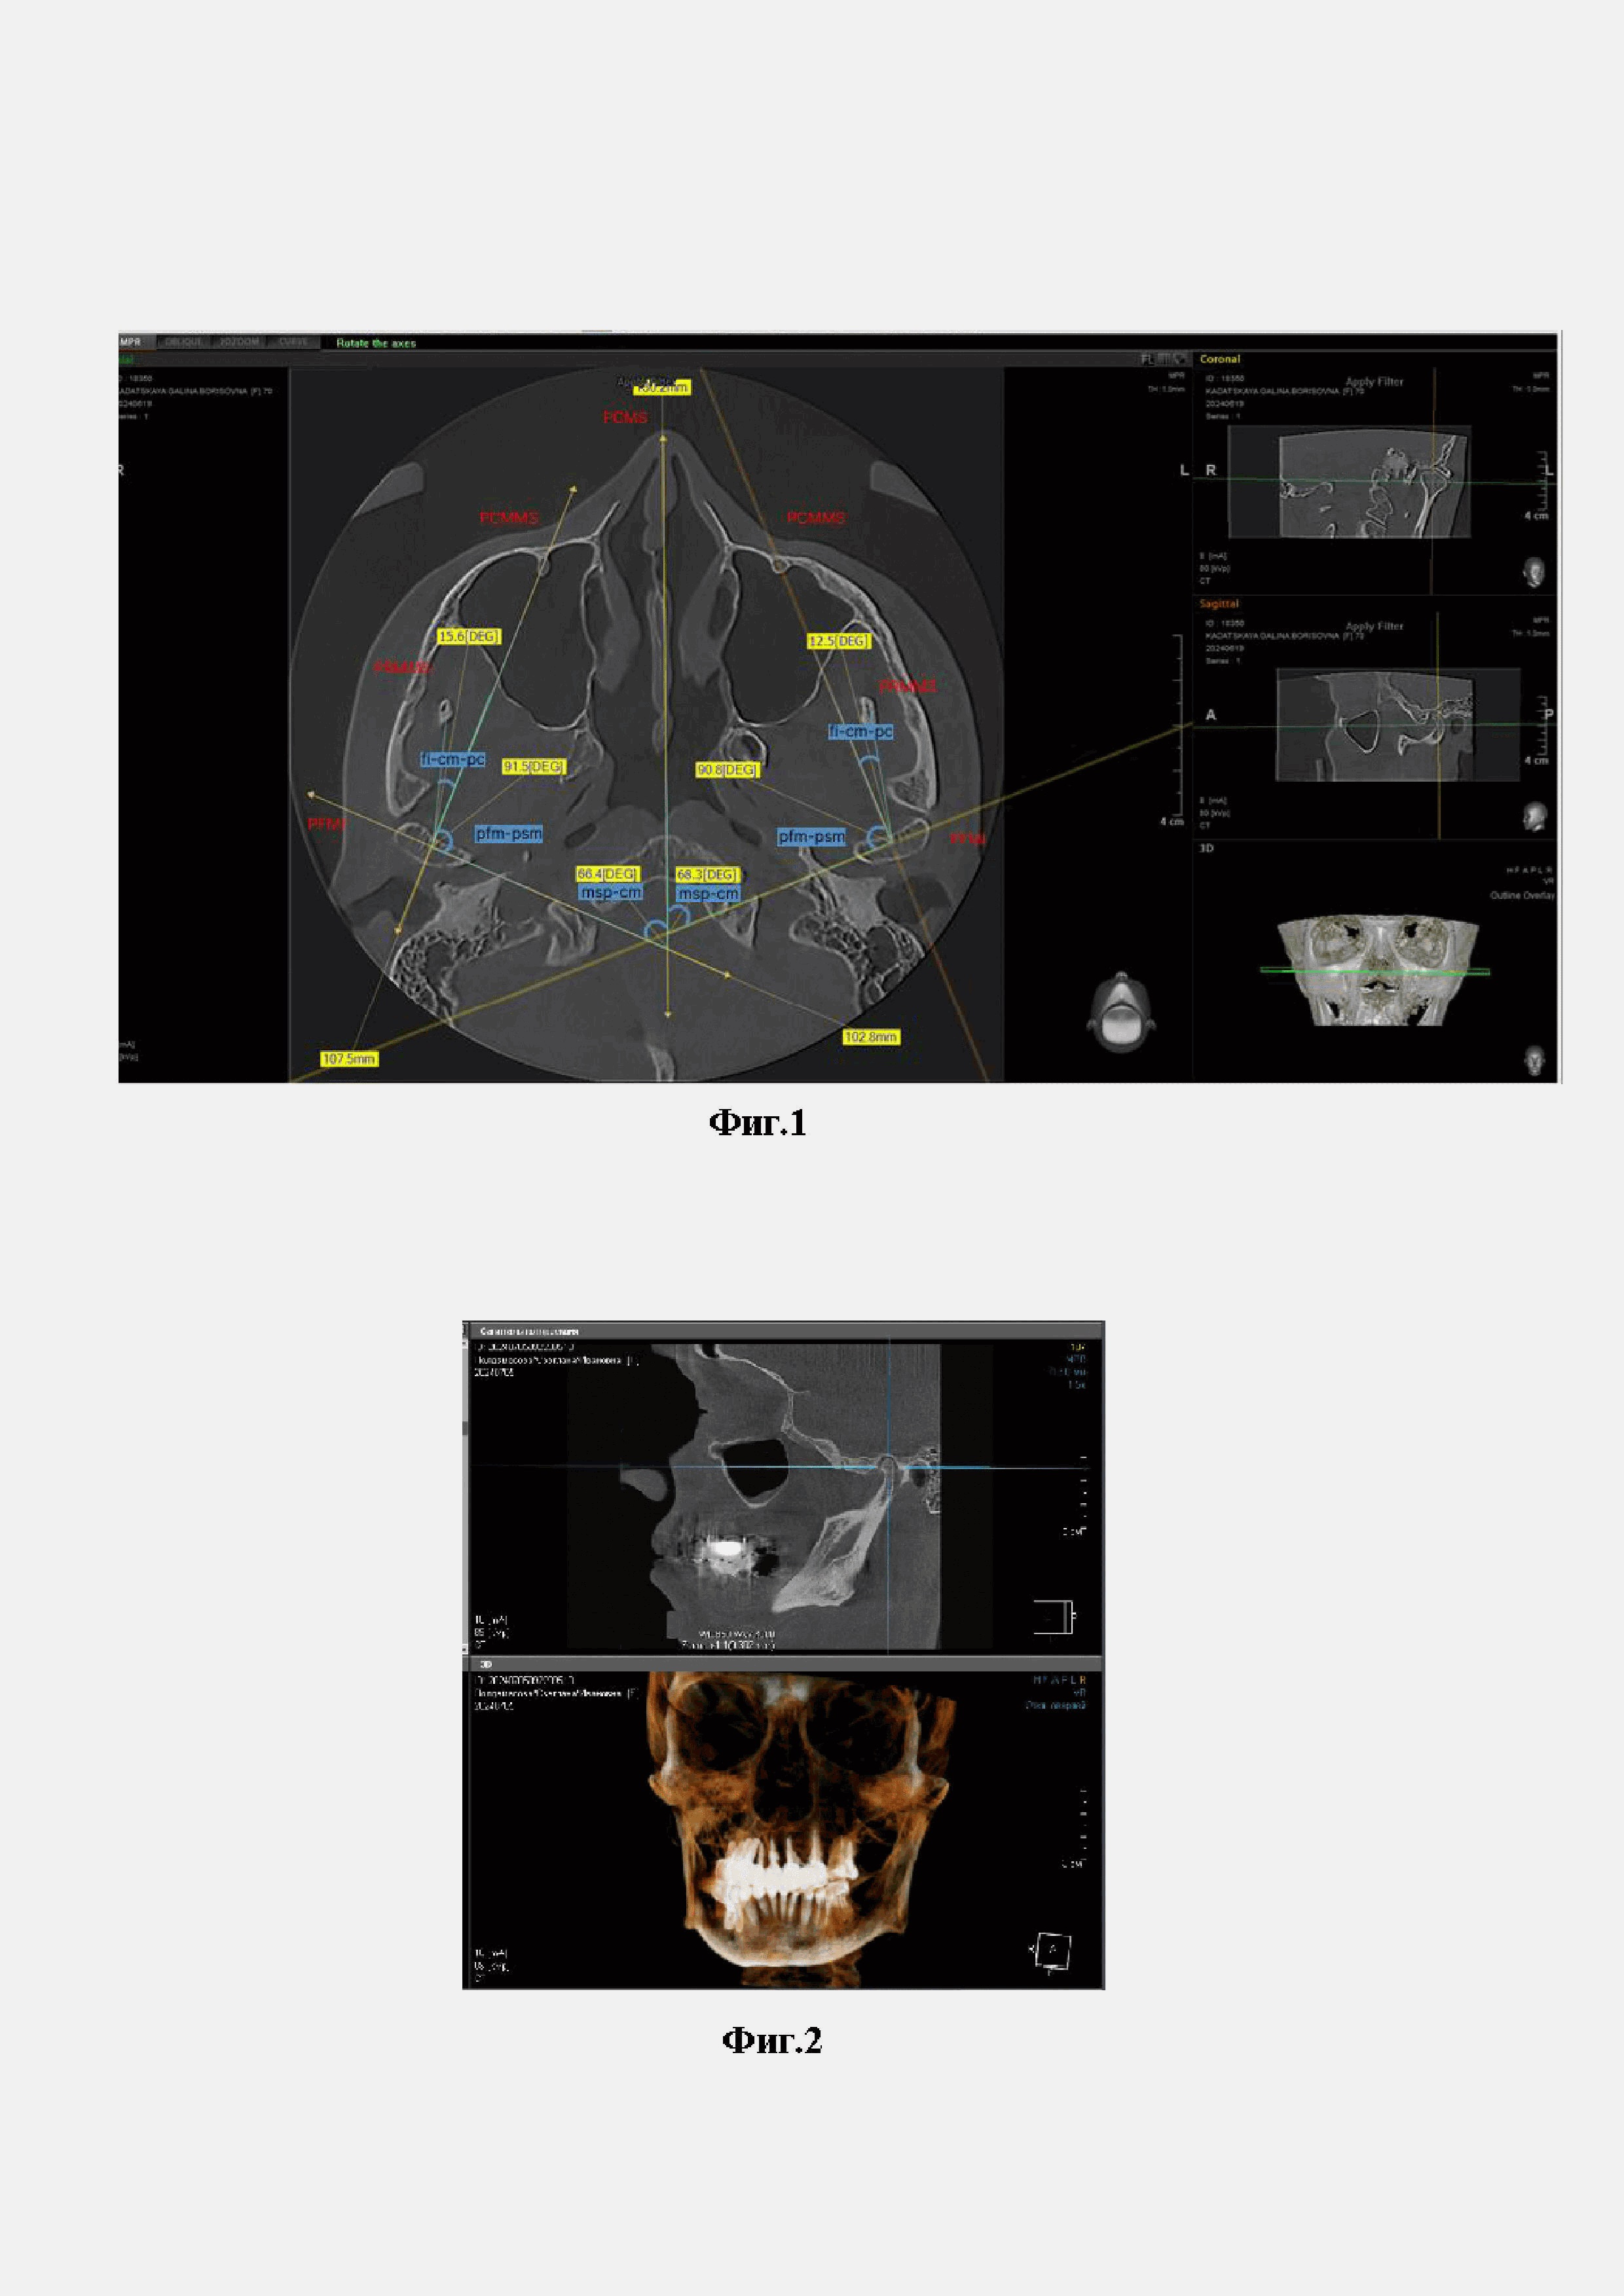

1. Определение краниометрических точек (фиг. 1)

В аксиальной проекции выявляют рентгеноанатомические ориентиры краниометрических точек. Алгоритм определения краниометрической точки по изображению костей черепа в аксиальной проекции КЛКТ включает: определение срединно-сагиттальной и фронтальной плоскостей ГНЧ и краниометрической точки ГНЧ, образованной точкой пересечения этих плоскостей; определение краниометрической точки венечного отростка нижней челюсти, сошника и клиновидной кости; построение по краниометрическим точкам рентгеноанатомических плоскостей; определение угловых зависимостей и устойчивых рентгеноанатомических взаимосвязей между построенными плоскостями. Таким образом, определяют топографию пяти краниометрических точек в аксиальной проекции черепа:

1.1. Краниометрическая точка ГНЧ (cáput mandibuláre - cm) - определяют топографию контуров ГНЧ в нижнечелюстной ямке височной кости. Затем с медиальной и латеральной стороны ГНЧ на поверхности выявляют вершины, максимально выступающие в полость нижнечелюстной ямки, отмечают их маркером. Соединяют прямой полученные точки и строят фронтальную ось ГНЧ. Фронтальную ось ГНЧ делят пополам и получают первую краниометрическую точку, являющуюся рентгенологической серединой фронтальной оси ГНЧ.

1.2. Краниометрическая точка (foramen infraorbitale - fi) - подглазничное отверстие: определяется в аксиальной проекции открывающимся устьем канала f. infraorbitale. на передней стенке верхнечелюстного синуса.

1.3. Краниометрическая точка (processus coronoideus - pc) - вершина венечного отростка нижней челюсти. Определяется в аксиальной проекции КЛКТ черепа.

1.4. Краниометрическая точка (pars cuneiformis vomeris - pcv) - клиновидная часть сошника, максимально выступающая вершина с латеральной поверхности в аксиальной проекции КЛКТ черепа.

1.5. Краниометрическая точка (corpus sphenoidale - cs) - тело клиновидной кости, максимально выступающая вершина с латеральной поверхности в аксиальной проекции КЛКТ черепа.

2. Построение рентгеноанатомических плоскостей по КЛКТ черепа в аксиальной проекции:

2.1. Срединно-сагиттальная плоскость ГНЧ (Planum cáput mandibuláre mid sagittalis - PCMMS) - строится через точки: cm - fi.

2.2. Срединно-сагиттальная плоскость ветви нижней челюсти (Planum ramus mandibulae mid sagittalis - PRMMS) - строится через точки: cm - pc. Венечный отросток (processus coronoideus - pc) и ветвь нижней челюсти располагаются в одной срединно-сагиттальной плоскости, в отличие от срединно-сагиттальной плоскости ГНЧ.

2.3. Срединно-сагиттальная плоскость черепа (Planum cranii mid sagittalis - PCMS) - строится через точки: латеральный край сошника - тело клиновидной кости. Для этого отмечают латеральный и медиальный края сошника, соединяют эти точки прямой и получают срединно-сагиттальную плоскость черепа.

2.4. Фронтальная плоскость головки нижней челюсти (Planum frontale mandibulae inferioris - PFMI) -с медиальной и латеральной стороны ГНЧ на поверхности выявляют вершины, максимально выступающие в полость нижнечелюстной ямки, отмечают их маркером и соединяют между собой.

Далее определяем углы, образованные при пересечении срединно-сагиттальных и фронтальных плоскостей (фиг.1).

3.4. Угол msp-cm равен слева 68.3°, справа 66.4°. Данный угол образован срединно-сагиттальной плоскостью черепа и фронтальной плоскостью ГНЧ. Данный угол показывает отношение положения головки нижней челюсти к костям мозгового отдела черепа.

3.5. Угол fi-cm-pc равен слева 12.5°, справа 15.6°. Данный угол образован пересечением срединно-сагиттальных плоскостей ГНЧ и ветви нижней челюсти. Значение этого угла позволяет определить угол отклонения срединно-сагиттальной плоскости ГНЧ от срединно-сагиттальной плоскости ветви нижней челюсти.

3.6. Угол pfm-psm, образованный срединно-сагиттальной и фронтальной плоскостями ГНЧ равен слева 90.8°, справа 91.5°.